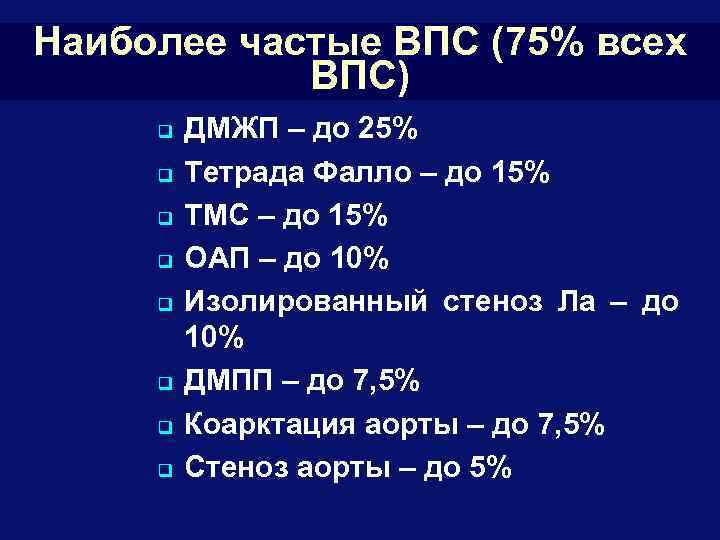

Наиболее частые ВПС (75% всех ВПС) q q q q ДМЖП – до 25% Тетрада Фалло – до 15% ТМС – до 15% ОАП – до 10% Изолированный стеноз Ла – до 10% ДМПП – до 7, 5% Коарктация аорты – до 7, 5% Стеноз аорты – до 5%